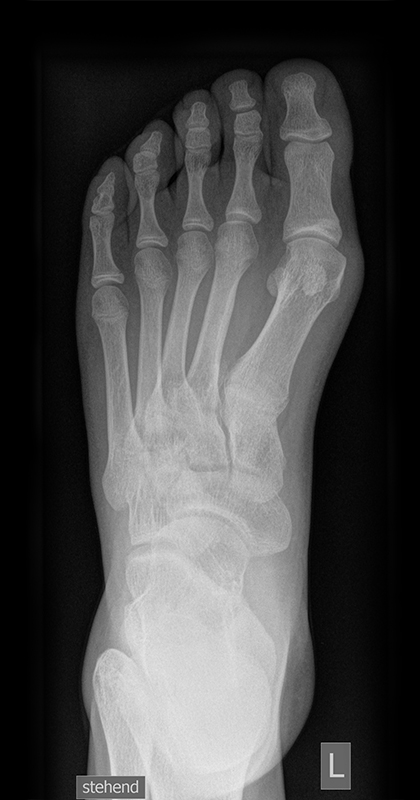

Die folgenden Bilder zeigen die belastete Röntgenaufnahmen des linken Fußes einer jungen Patientin zu Beginn der Therapie und nach 6 Monaten Training. Erkennbar ist die höhere muskuläre Verspannung des Fußes mit verbesserter Stellung der milden Hallux valgus Deformität.

Zum Lesen der Bildbeschreibung und zur Vollansicht bitte die Bilder anklicken.